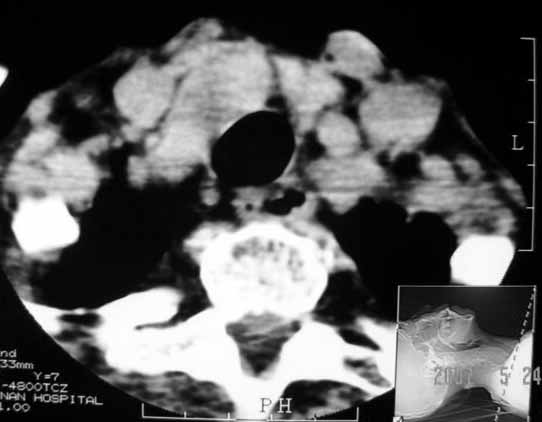

以下是引用jw-830在2007-5-24 15:33:00的发言:[br]右侧甲状腺增大,内可见低密度,病灶与周围软组织界线欠清晰,建议增强扫描除外甲状腺癌

以下是引用adams在2007-5-24 17:15:00的发言:[br]支持“ 右侧甲状腺增大,内可见低密度,病灶与周围软组织界线欠清晰,建议增强扫描除外甲状腺癌”。 [br] [br] [br][br] [br] [br]

以下是引用苯小孩在2007-5-24 15:26:00的发言:[br]左侧甲状腺腺癌或瘤,建议穿刺或核素进一步检查.